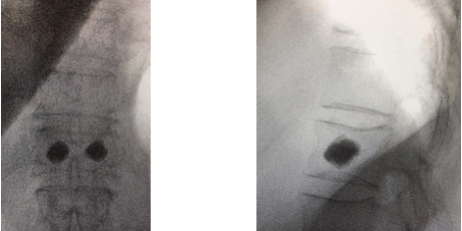

A cifoplastia foi elaborada para a estabilização cirúrgica das fraturas vertebrais por osteoporose torácicas e/ou lombares ocorridas dentro de três meses do início da dor ou da fratura (indicação chave).

Em casos induzidos pelo uso de esteroides, o tempo pode ser estendido até 6 meses da fratura. É indicada principalmente quando há dor grave que interfere nas atividades do paciente, quando a dor não é controlada por medicamentos analgésicos orais ou quando a dor é localizada no nível da fratura. Muitos pacientes com fraturas vertebrais por osteoporose de 3 a 6 meses também podem realizar a cifoplastia devido a fraturas subagudas dentro do corpo vertebral osteoporótico, que é remodelado pela cifoplastia. Também pode ser indicada em casos de hemangiomas vertebrais que causam colapsos vertebrais ou déficits neurológicos como resultado da extensão interna do canal espinal e fraturas patológicas por compressão causadas por metástases.